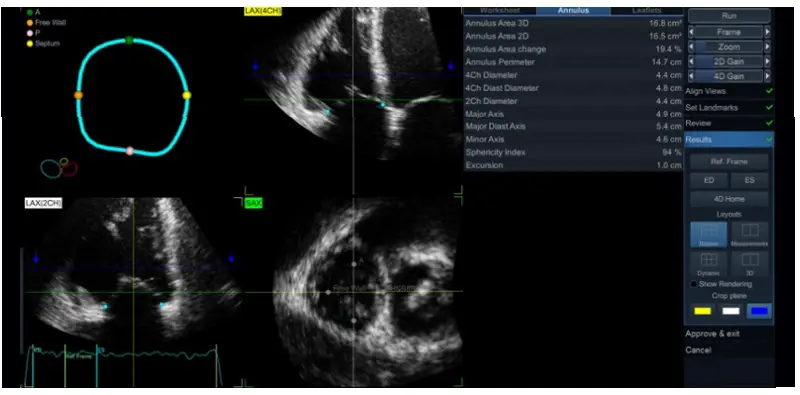

Results - Quantitative measures are shown in 3 different pages: Worksheet (summarizing the most used among annulus and leaflets parameters), Annulus (Figure 8) and Leaflets.

Figure 8. Annulus measurements menu using 4D Auto TVQ tool. - Display can be changed among various options: Biplane (default), Measurements (no images), 3D (showing both 3D model and measurements) and Dynamic (showing also the graphic of the dynamic changes of different annulus parameters).